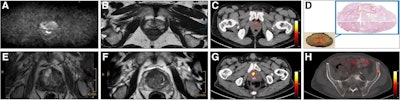

Axial views of exemplary case studies in which additional PSMA PET/CT changed prostate cancer (PCa) management. (A–D) A 68-year-old man with isolated PSA elevation had no tumor-suggestive findings on mpMRI (A and B), but they were high suggestive of PCa on PSMA-PET/CT (C). After radical prostatectomy, 22-mm index tumor identified on PSMA- PET/CT was confirmed with Gleason score of 7a (D). Reviewers without PSMA-PET/CT information (MRI-only pathway) recommended continued PCa screening, whereas reviewers with PSMA PET/CT knowledge suggested active treatment. (E–H) A 72-year-old man with PSA of 9.1 ng/mL and suggestive prostate palpation had highly suggestive PCa lesion on both mpMRI (E and F) and PSMA-PET/CT (G). PSMA-PET/CT also detected two small osseous metastases in left ilium (H) and sacrum. Management recommendations varied: local therapy (surgery or radiation) without PSMA PET/CT knowledge versus androgen deprivation therapy and radiation for primary tumor and metastases with PSMA-PET/CT knowledge.Axial views of exemplary case studies in which additional PSMA PET/CT changed prostate cancer (PCa) management. (A–D) A 68-year-old man with isolated PSA elevation had no tumor-suggestive findings on mpMRI (A and B), but they were high suggestive of PCa on PSMA-PET/CT (C). After radical prostatectomy, 22-mm index tumor identified on PSMA- PET/CT was confirmed with Gleason score of 7a (D). Reviewers without PSMA-PET/CT information (MRI-only pathway) recommended continued PCa screening, whereas reviewers with PSMA PET/CT knowledge suggested active treatment. (E–H) A 72-year-old man with PSA of 9.1 ng/mL and suggestive prostate palpation had highly suggestive PCa lesion on both mpMRI (E and F) and PSMA-PET/CT (G). PSMA-PET/CT also detected two small osseous metastases in left ilium (H) and sacrum. Management recommendations varied: local therapy (surgery or radiation) without PSMA PET/CT knowledge versus androgen deprivation therapy and radiation for primary tumor and metastases with PSMA-PET/CT knowledge.Journal of Nuclear Medicine